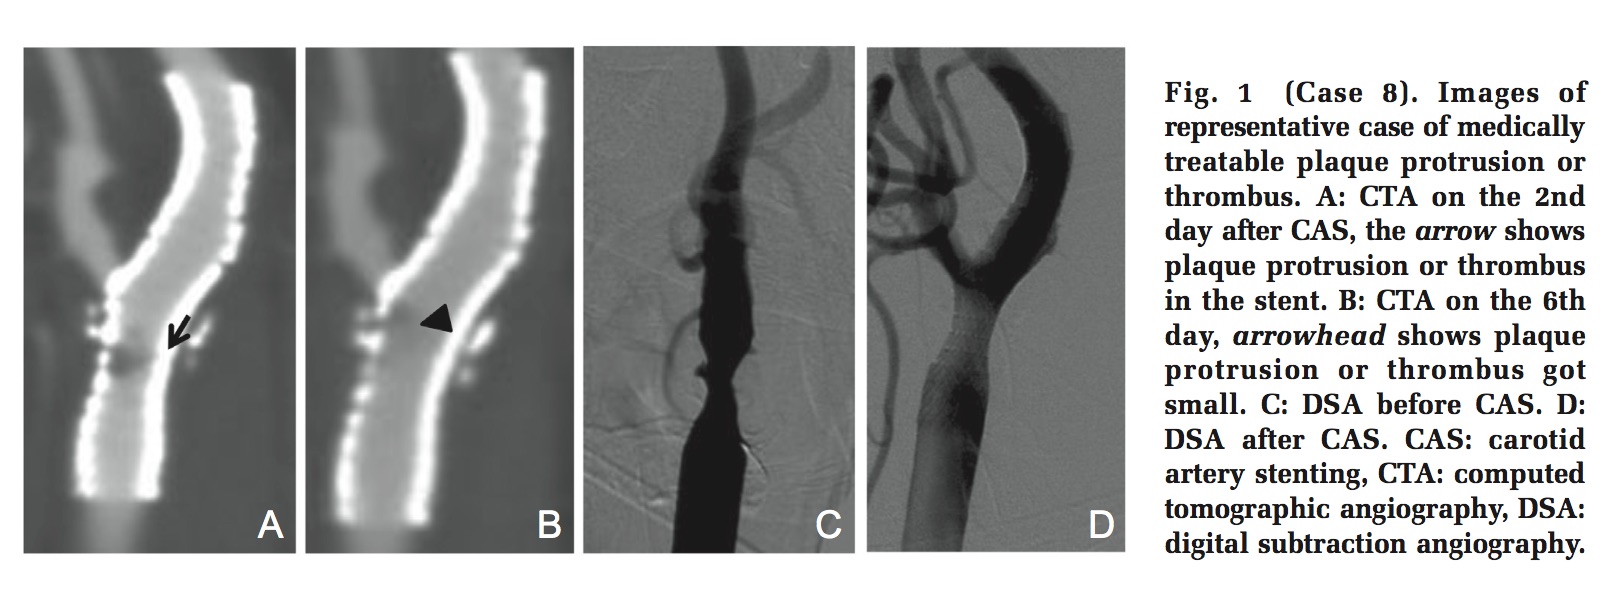

この観察研究では,CAS施行後にCTアンギオや頸動脈エコー検査を用いてステント内血栓やプラークプロトリュージョンの頻度について調査し,そのリスクファクターを検討している.この論文で注目に値する点は,これまでもCAS手技中(ステント留置直後)にプラークプロトリュージョンを認めた症例の報告は少なからずあるが,CAS施行後しばらくしてから生じているプロトリュージョンを評価している点である.その結果CASを施行した全32症例のうち8例に,CAS施行後,CTアンギオおよびエコー検査においてプラークプロトリュージョンが認められている.検討によると,プロトリュージョンを認めた患者群では症候性病変およびプラークの潰瘍形成が有意に多く認められている(写真1).プロトリュージョンを認めた8症例に対しては,抗凝固療法や抗血小板薬の追加投与などが行われているが、興味深いことに,そのほとんどの症例で血栓およびプロトリュージョンプラークの退縮を認めている(写真2).薬物療法によっても退縮しなかった症例に対してのみ,追加のステント治療が施行されている.この症例においては,再治療時にIVUSが施行されており,あきらかなプロトリュージョンを確認することが出来る(写真3).すべての症例においてステント留置直後にIVUSが施行されているので,プロトリュージョンはステント留置後,数時間から数日で生じていると解釈できる.CAS後プロトリュージョンを認めた8症例のいずれも遅発性の脳梗塞や一過性脳虚血発作は認めていないため,このステント内血栓やプラークプロトリュージョンが遅発性合併症の原因と断定することは出来ないが,その関連は強く予想される.

写真2